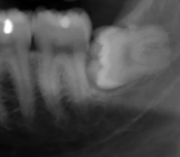

The procedure, depending on the depth of the impaction and angle of the tooth, is to create an incision in the mucosa of the mouth, remove bone of the mandible or maxilla adjacent the tooth, section the tooth and extract it in pieces. This can be completed under local anaesthetic, sedation or general anaesthetic.

Coronectomy

Coronectomy is a procedure used when the surgeon believes that there is a high risk of inferior alveolar nerve injury. After making the incision in the mucosa and removing bone adjacent the tooth, the crown is cut and removed with no attempt at removing the roots. It is indicated when there is no disease of the dental pulp or infection around the crown of the tooth and there is a high risk of inferior alveolar nerve injury.